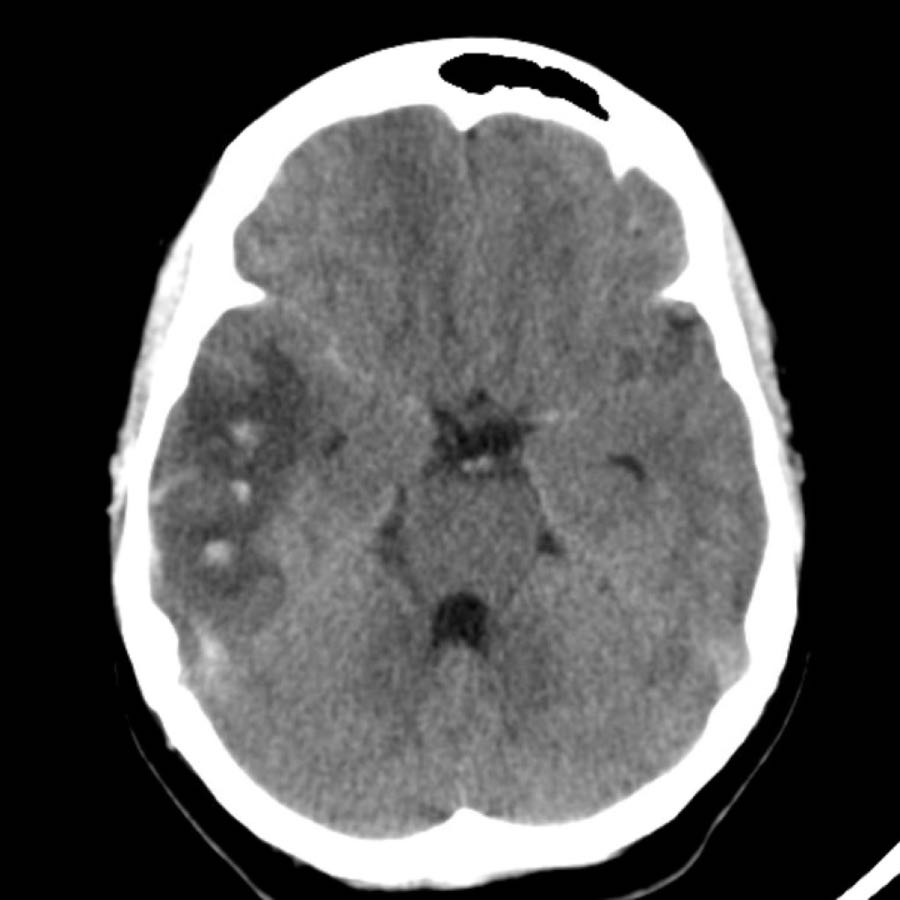

Bệnh nhân này được nhập vào đơn vị đột quỵ với chẩn đoán nhồi máu não mới trong vùng phân bố của động mạch não giữa trái.

Do đến viện muộn, ngoài cửa sổ điều trị tiêu huyết khối, bệnh nhân không được chỉ định liệu pháp này.

CT không tiêm thuốc cản quang (NECT) tái khám (hình A) được chỉ định do tình trạng lâm sàng xấu đi, cho thấy vùng giảm tỷ trọng giới hạn rõ trong vùng phân bố của động mạch não giữa trái. Trong vùng giảm tỷ trọng này, ghi nhận các ổ tăng tỷ trọng nhỏ, mờ nhạt.

MRI thực hiện vài giờ sau trong cùng ngày cho thấy các ổ xuất huyết (mũi tên) phù hợp với hình ảnh chuyển dạng xuất huyết dạng chấm xuất huyết (petechial) của ổ nhồi máu thiếu máu cục bộ.